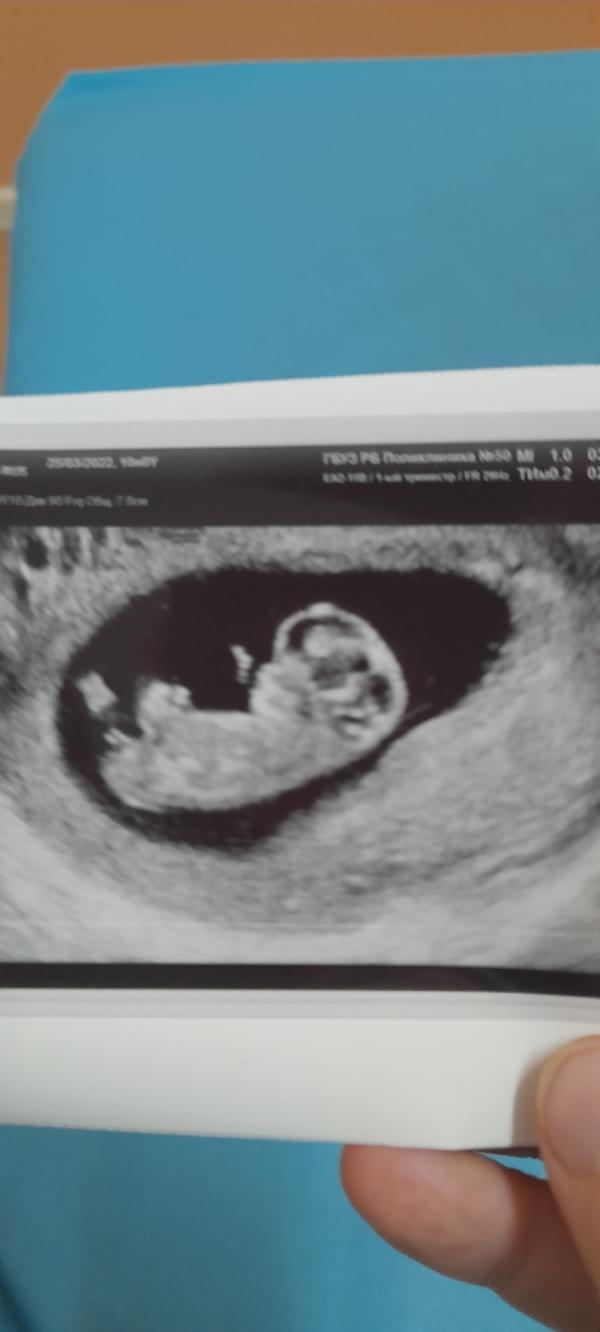

А разве на 10 недель можно пол хотябы предположить? Сходила платно убедиться что все нормально. В итоге все хорошо, все по нормам, предположили девочку 🤔

Там по прикреплению как то определяют, с права или лева. Метод не помню как называется.Мне в 8 недель сказали скорее всего девочка так и получилось. Я потом гуглила)

На 9 неделе только формируются половые признаки, поэтому вряд ли так рано